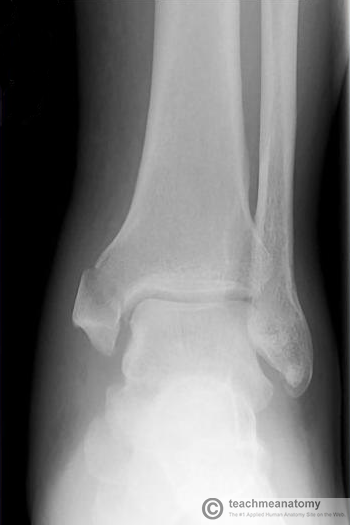

What has happened here?

How is it caused?

Medial Malleolus fracture

Caused by ankle twisting inwards (overinversion), the talus of the foot is forced against the medial malleolus, causing a spiral fracture